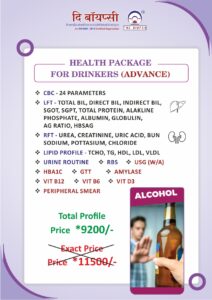

Our Health Packages

We Provide All Types of Diagnostics Services and its Health Pacakages also.